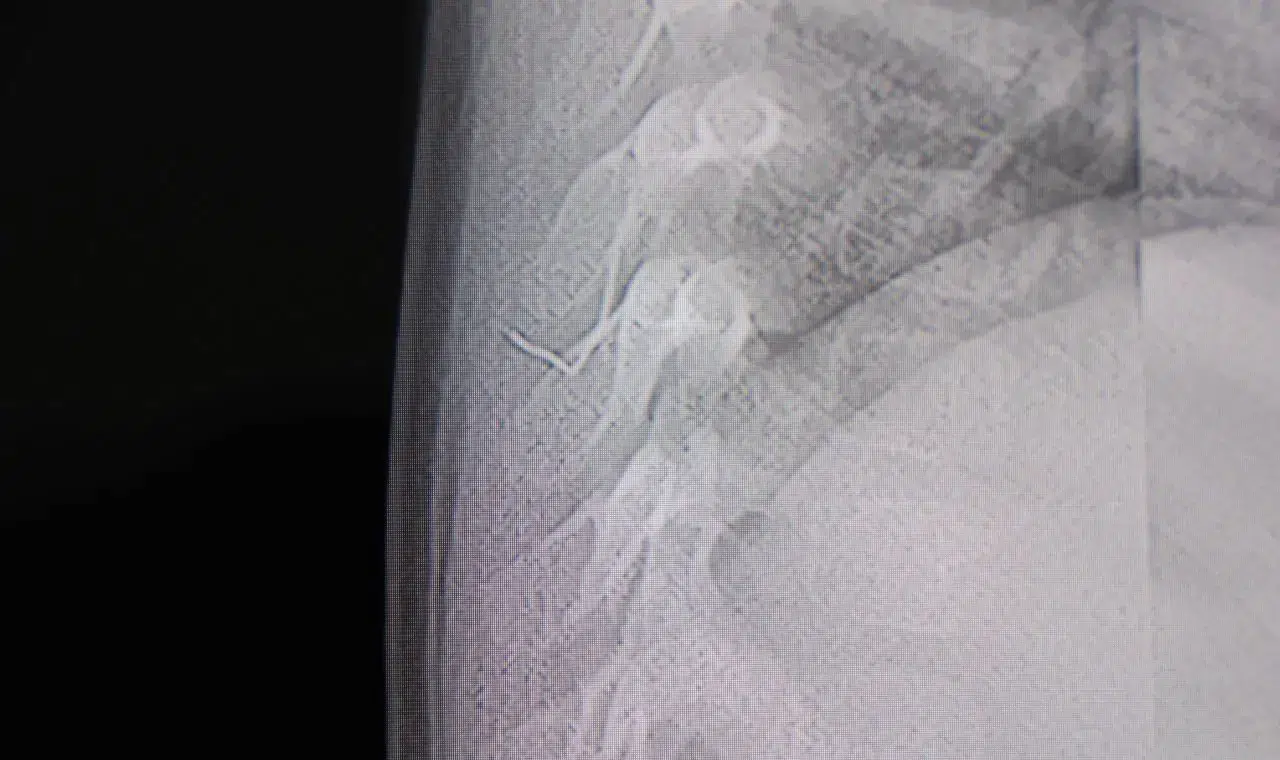

Kahramanmaraş'ta sırt üstü yatmak istemeyen, yatırıldığında ağlama ve huzursuzluğu nedeniyle hastaneye götürülen bir yaşındaki bebeğin sırtından akciğer zarına doğru ilerleyen 2 santimetrelik zımba teli çıktı.

Alınan bilgiye göre, Kahramanmaraş'ta farklı ortopedi, çocuk cerrahisi ve beyin cerrahisi kliniklerine başvurusu yapılan bir yaşındaki bebeğin, sırt bölgesinde yabancı bir cisim olduğu ancak müdahalenin zor olduğu ve 8 yaşına kadar beklenmesi gerektiği bildirildi. Aile, bebekleri için son olarak HG Hospital'e başvurdu. HG Hospital Beyin ve Sinir Cerrahisi Uzmanı Prof. Dr. İdris Altun tarafından yapılan tetkiklerde, yabancı cismin cilt altında, omurilik kanalına yakın bir bölgede olduğu ve akciğer zarına doğru ilerlediği belirlendi. Hasta, genel anesteziye alınmadan, lokal anestezi ve sedasyon eşliğinde ameliyata alındı. Yapılan müdahalede yabancı cisim tamamen çıkarıldı. Çıkarılan cismin, ince zımba teline benzer metal bir tel olduğu ve yaklaşık 2 santimetre uzunluğunda bulunduğu tespit edildi. Hasta, aynı gün taburcu edildi.

Konuya ilişkin açıklama yapan Prof. Dr. İdris Altun, "Sırtında yabancı bir cisim olduğu söylenmiş ancak çıkarılamayacağı ve 8 yaşına kadar beklenmesi gerektiği ifade edilmişti. Bize başvurduğunda yaptığımız tetkiklerde, cilt altında, omurilik kanalına çok yakın ve akciğer zarına doğru ilerleyen bir yabancı cisim tespit ettik. Hastamızı tamamen uyutmadan, lokal anestezi ve sedasyon eşliğinde müdahale ederek lezyonu tamamen çıkardık. Çıkardığımız cismin ince zımba teline benzer, yaklaşık 2 santimetre uzunluğunda metal bir tel olduğunu gördük. Bu yabancı cisim alınmasaydı, bölgede enfeksiyon gelişebilirdi. Enfeksiyon sonucu omurilik kanalında ciddi hasarlar oluşabilir, çocuk büyüdükçe cismin hareket etmesine bağlı olarak omurilikte zedelenmeler meydana gelebilirdi. Ayrıca yana doğru ilerleyerek akciğer zarına ve akciğere batma riski vardı. Bu da enfeksiyona ve ilerleyen süreçte tümörle karışabilecek tablolara neden olabilirdi. Şu an hastamız gayet sağlıklı. Gerekli kontrolleri yaptık ve aynı gün taburcu ettik" dedi.